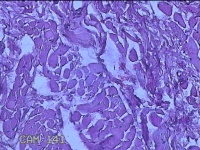

前额部结节

性别

男

年龄

26岁

临床诊断

皮脂腺囊肿

一般病史

发现前额部结节3年余。

标本名称

大体所见

灰白暗红色结节0.8x0.7x0.2cm一个,表面糜烂。